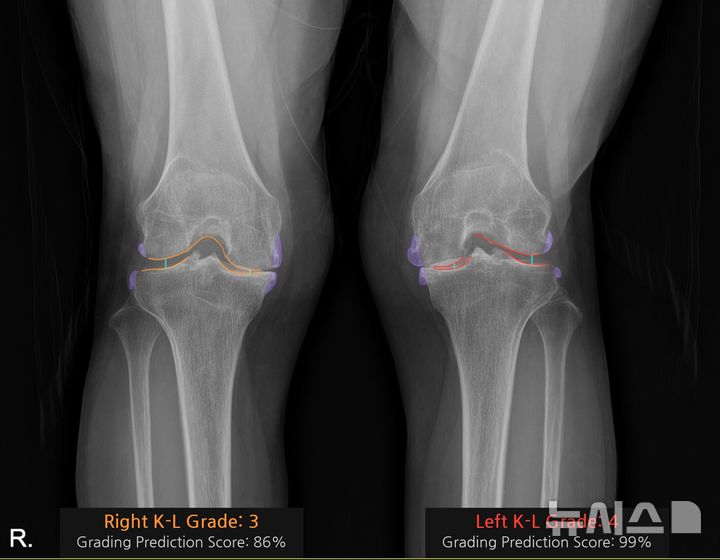

양쪽 무릎 수술을 고려했던 박씨는 왼쪽 무릎에서 관절 사이의 협착과 큰 골극, 심한 뼈 변형을 확인하고 의료진과 상의 끝에 동시 수술보다는 수술이 더 시급한 우선 왼쪽 무릎을 먼저 수술하기로 했다.

박씨는 “무릎 사진을 찍었는데 닳은 부위를 색깔로 구분해 보여주니 왼쪽 무릎 상태가 더 안좋은 게 바로 이해가 됐다”며 “세상이 점점 좋아진다”고 말했다.

식품의약품안전처로부터 의료기기 사용허가를 받은 ‘코네보 코아’는 환자의 무릎 엑스레이(X-ray) 영상을 10초 만에 분석해 K-L(Kellgren–Lawrence) 등급별색상으로 관절염의 심각도를 직관적으로 시각화한다. 화면에는 손상 부위의 골극(뼈 돌기)과 관절 간격이 색상으로 표시돼, 환자 본인도 상태를 한눈에 이해할 수 있다.